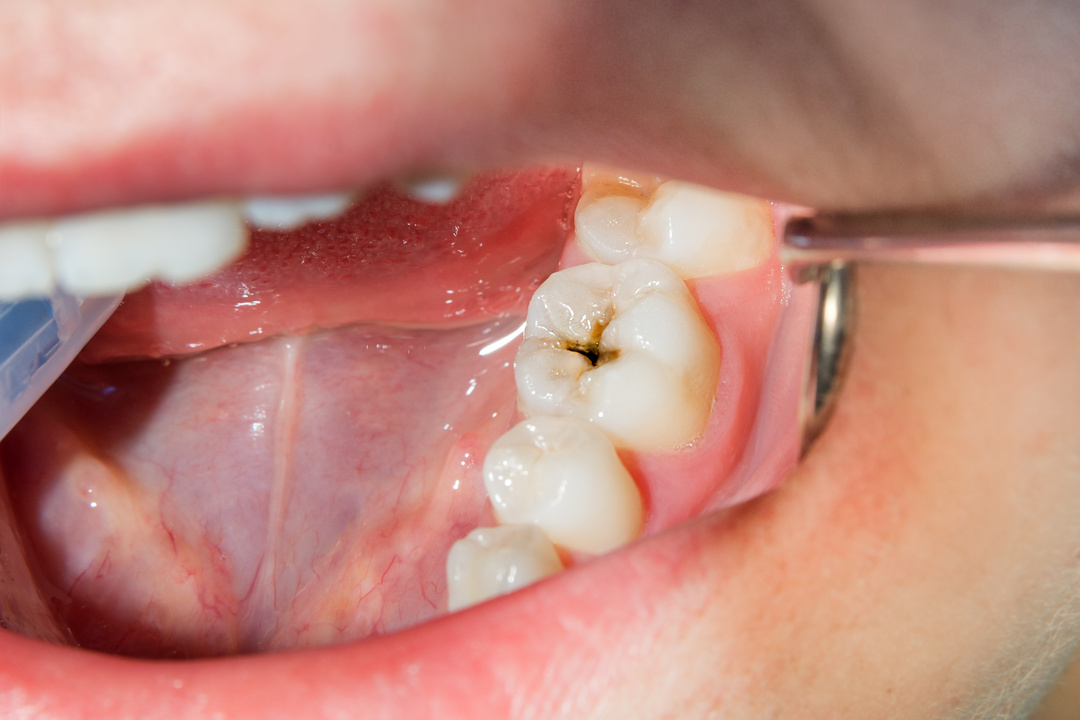

Les Caries dentaires

Comprendre les Caries Dentaires Par Dr KAHLOUN, mis à jour le 09/04/2024 à 13h21 Temps de lecture : ~ 10 minutes Facebook Twitter WhatsApp Email Sommaire Introduction... Lire la suite.